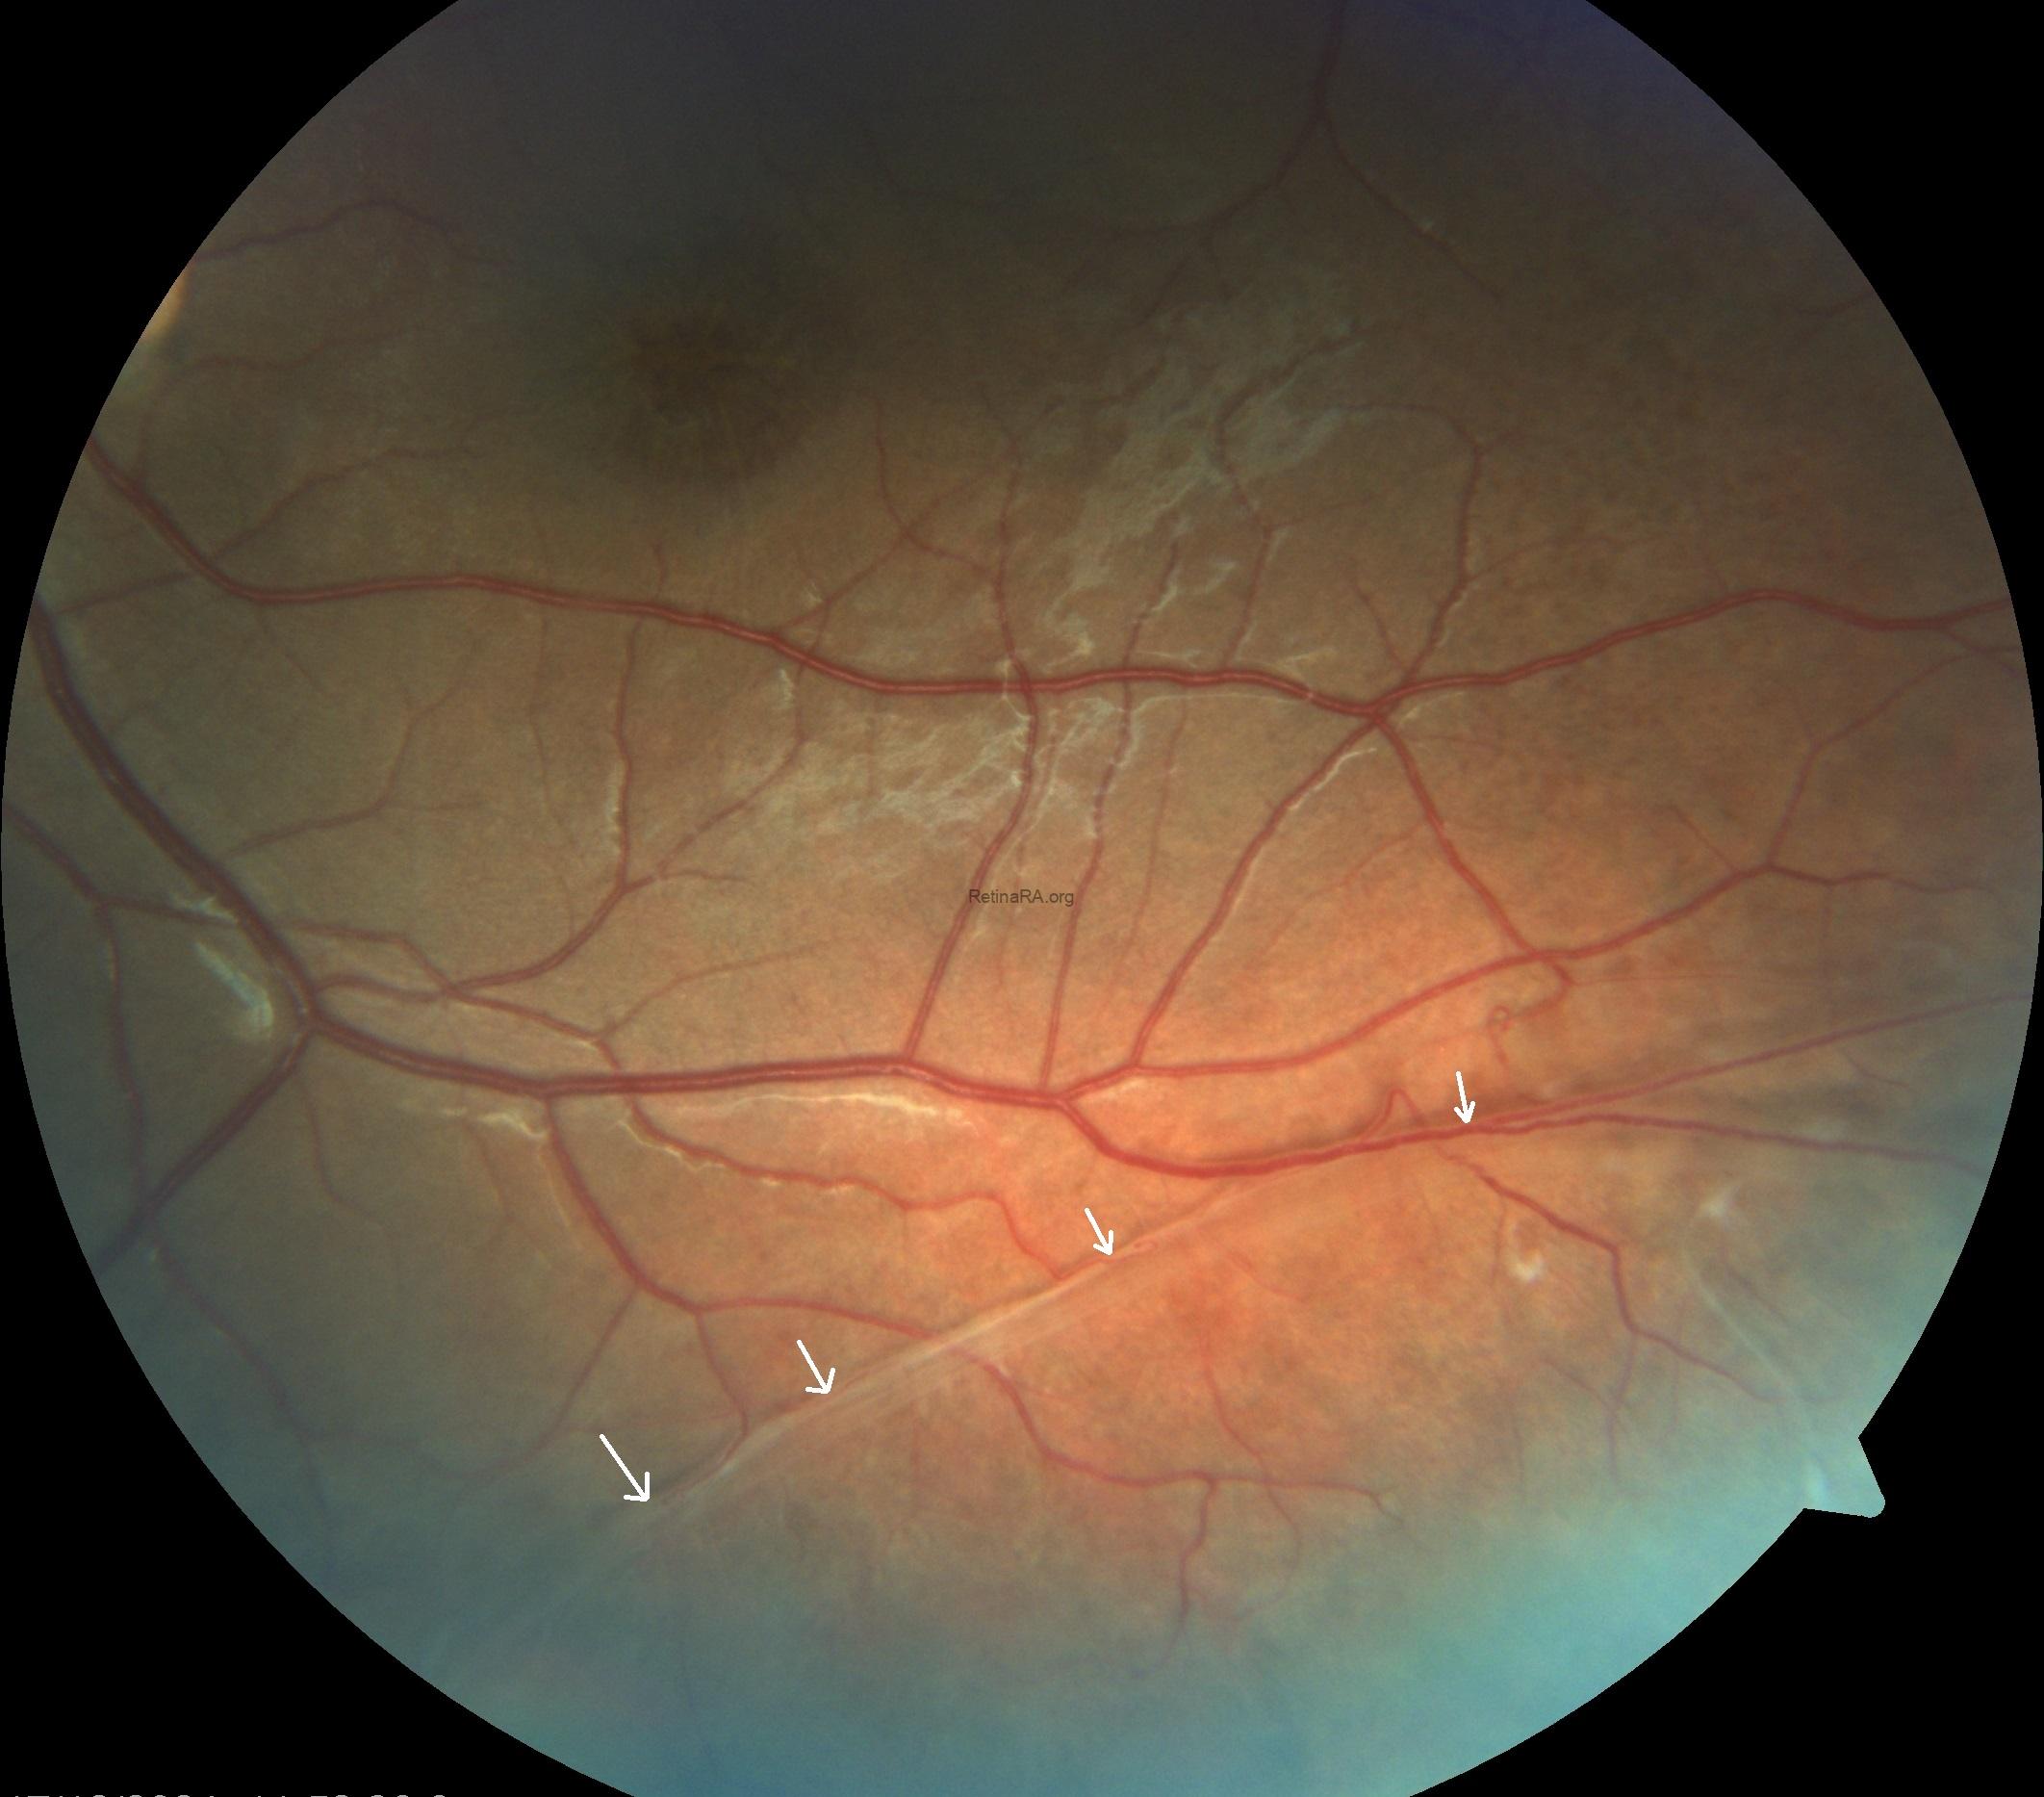

Fundus imaging revealed an abnormal foveal reflex with cystic lesions in both maculae. The right eye showed peripheral old laser scars and dome-shaped schisis, while the left eye demonstrated foveal schisis with a characteristic spoke-wheel pattern radiating from the fovea, along with an inferotemporal peripheral schisis.

Based on these multimodal imaging findings, a preliminary diagnosis of X-linked retinoschisis was made, which was later confirmed by genetic testing revealing an RS1 gene mutation.